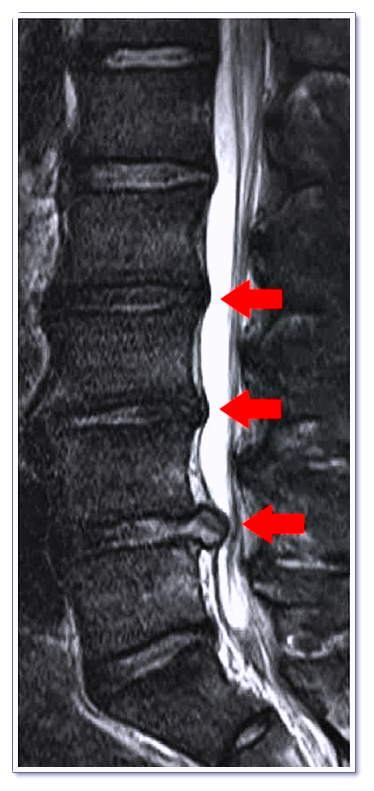

허리디스크는 단순히 ‘디스크가 튀어나온 질환’으로만 볼 수 없습니다.

척추뼈 사이에 위치한 추간판(디스크)은 충격을 흡수하고 척추의 유연성을 유지하는 역할을 하죠.

문제는 디스크가 돌출되면 그 주변 신경을 자극하면서 통증과 방사통이 생긴다는 점이에요.

이 통증은 허리에만 머물지 않고 다리나 발목까지 내려오기도 합니다.